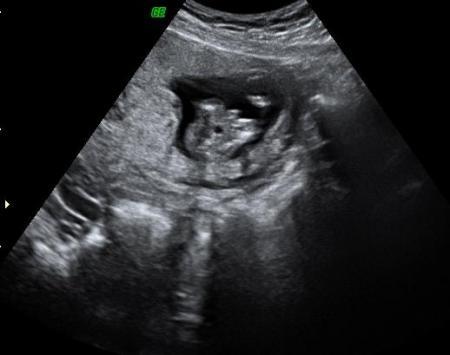

bin noch etwas unsicher, habe nun zwar von zwei ärtzen gehört das es ein junge werden soll hatte aber eher ein mädchen bauchgefühl, obowhl ein junge mein totaler wunsch gewesen wäre... habe letzte mal ein besseres bild bekommen aber sende mal das von heute... ansicht ist von unten ( popo, beine angewinkelt, volle blase und das zwischen den beinen soll der beweis sein).. was meint ihr?

Muss ja mal ganz doof fragen: der lange, breite "Strich" in der Mitte, der nach unten zeigt? Wenn ja, dann wär das ja riesig, oder?!? Also wir bekommen auch aller Wahrscheinlichkeit nach einen Jungen, aber unser Bild sieht anders aus (klar, auch anders aufgenommen). Also, wenn es das sein soll, dann eindeutig Junge lG, August-Wurmi